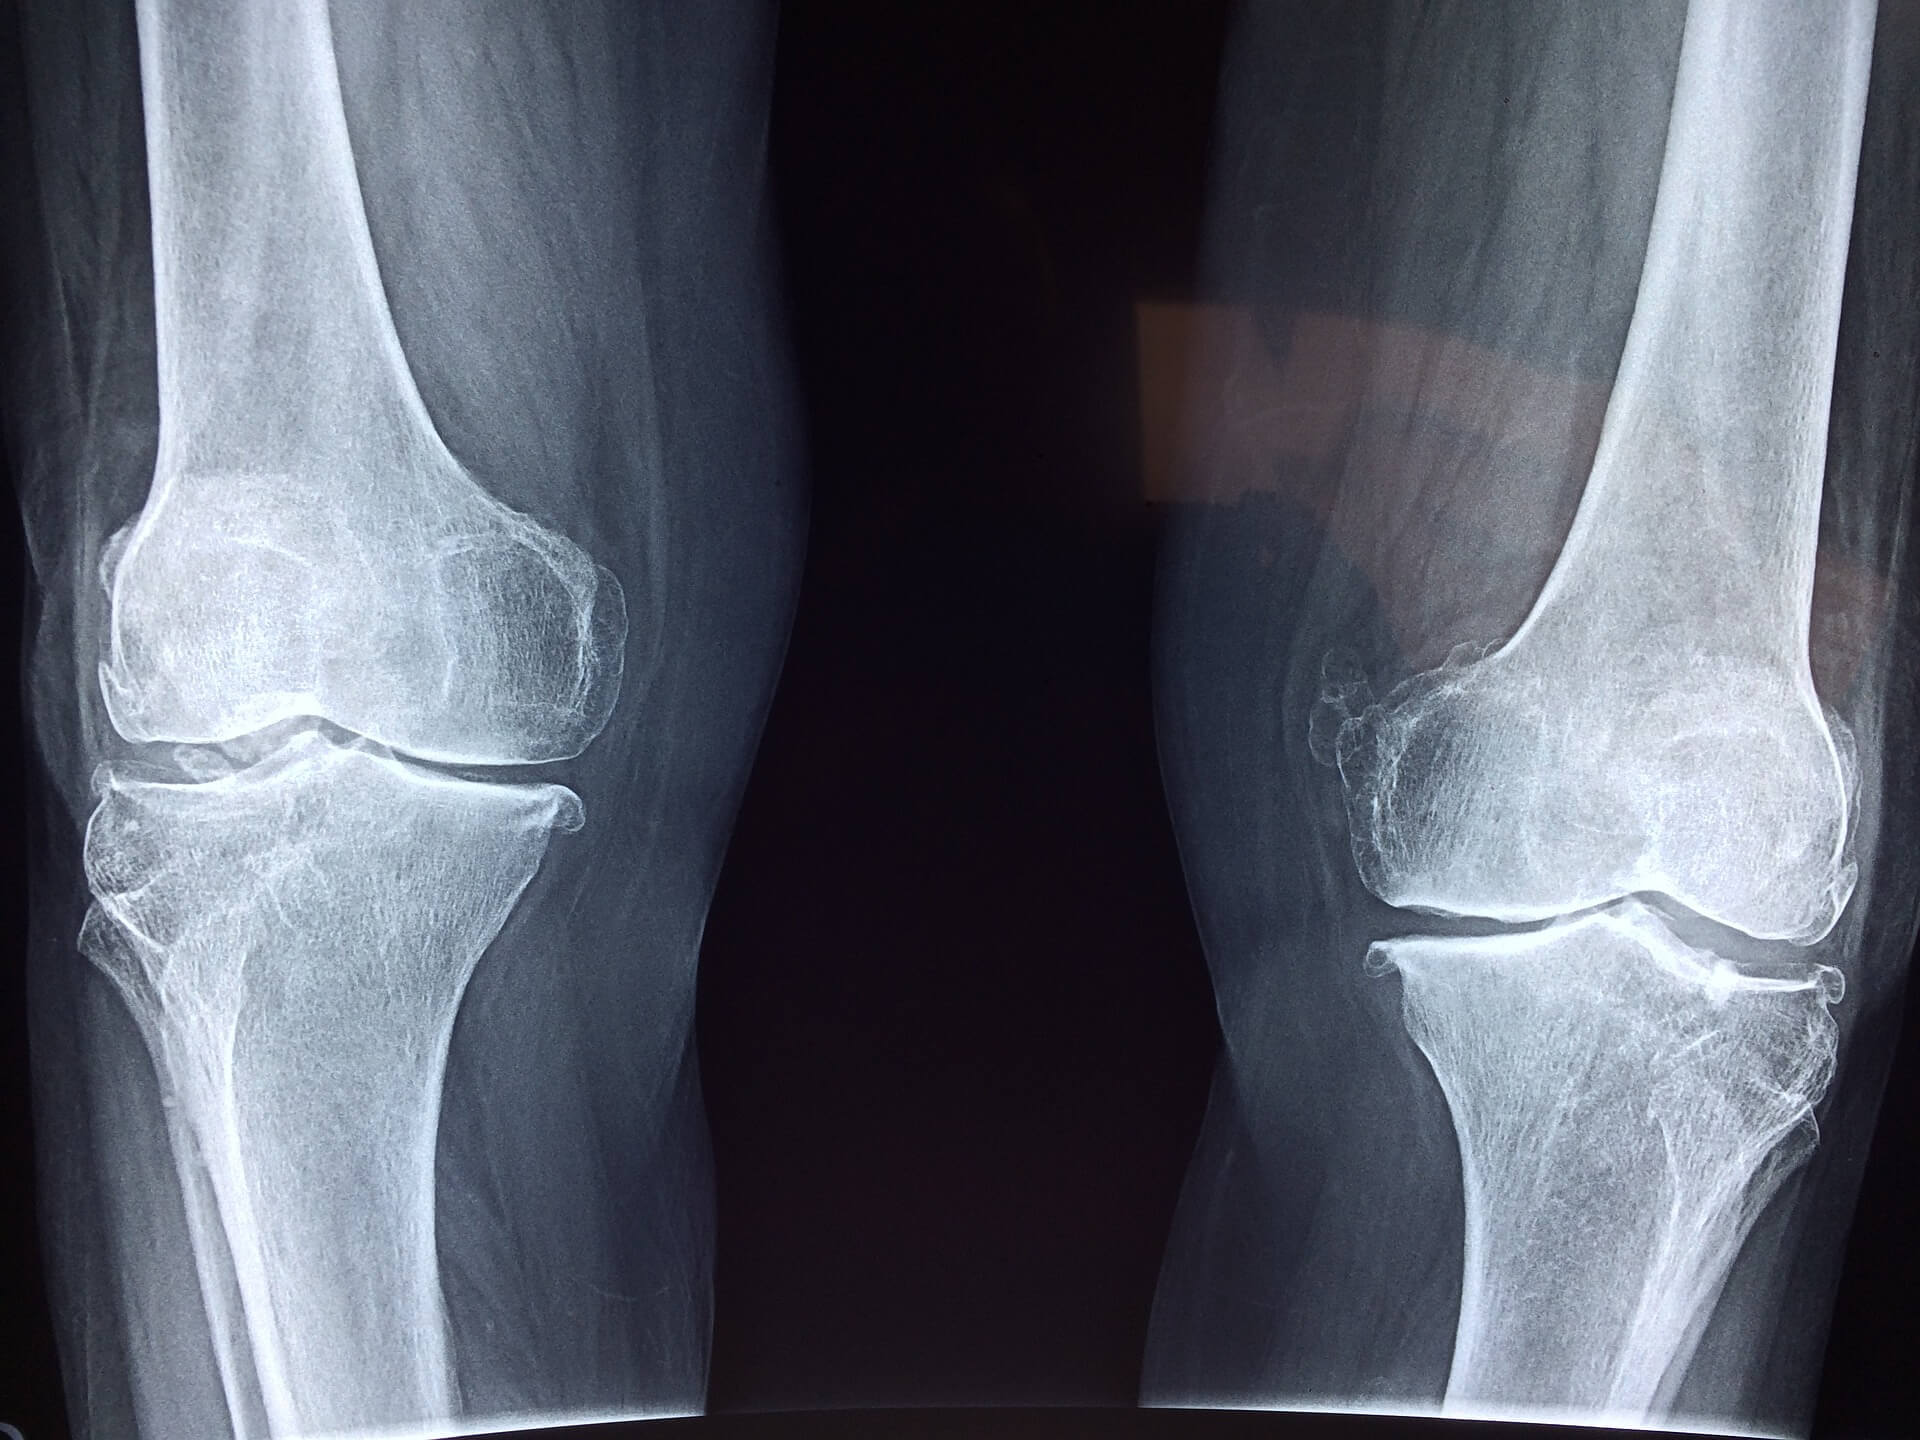

무릎 골관절염을 치료하는 방법

무릎 골관절염의 치료는 모든 사람의 증상의 강도에 따라 달라지며 약물이나 심지어 수술이 필요할 수도 있다고 합니다. 어쨌든, 약물치료는 확실히 대부분 증상을 완화할 수 있습니다.